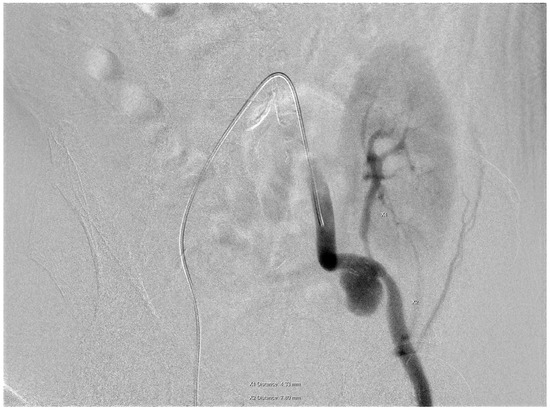

- Bypass grafting ensured continuous perfusion to the lower limb, mitigating the risk of ischemic complications;

- Endovascular stenting minimized surgical trauma while effectively excluding the pseudoaneurysm;

- Coil embolization provided an additional layer of pseudoaneurysm isolation, further enhancing treatment efficacy.